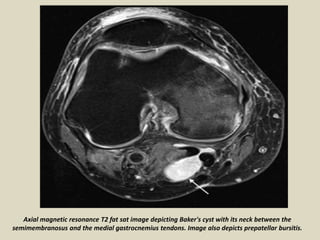

Axial magnetic resonance T2 fat sat image depicting Baker's cyst with its neck between the

semimembranosus and the medial gastrocnemius tendons. Image also depicts prepatellar bursitis.